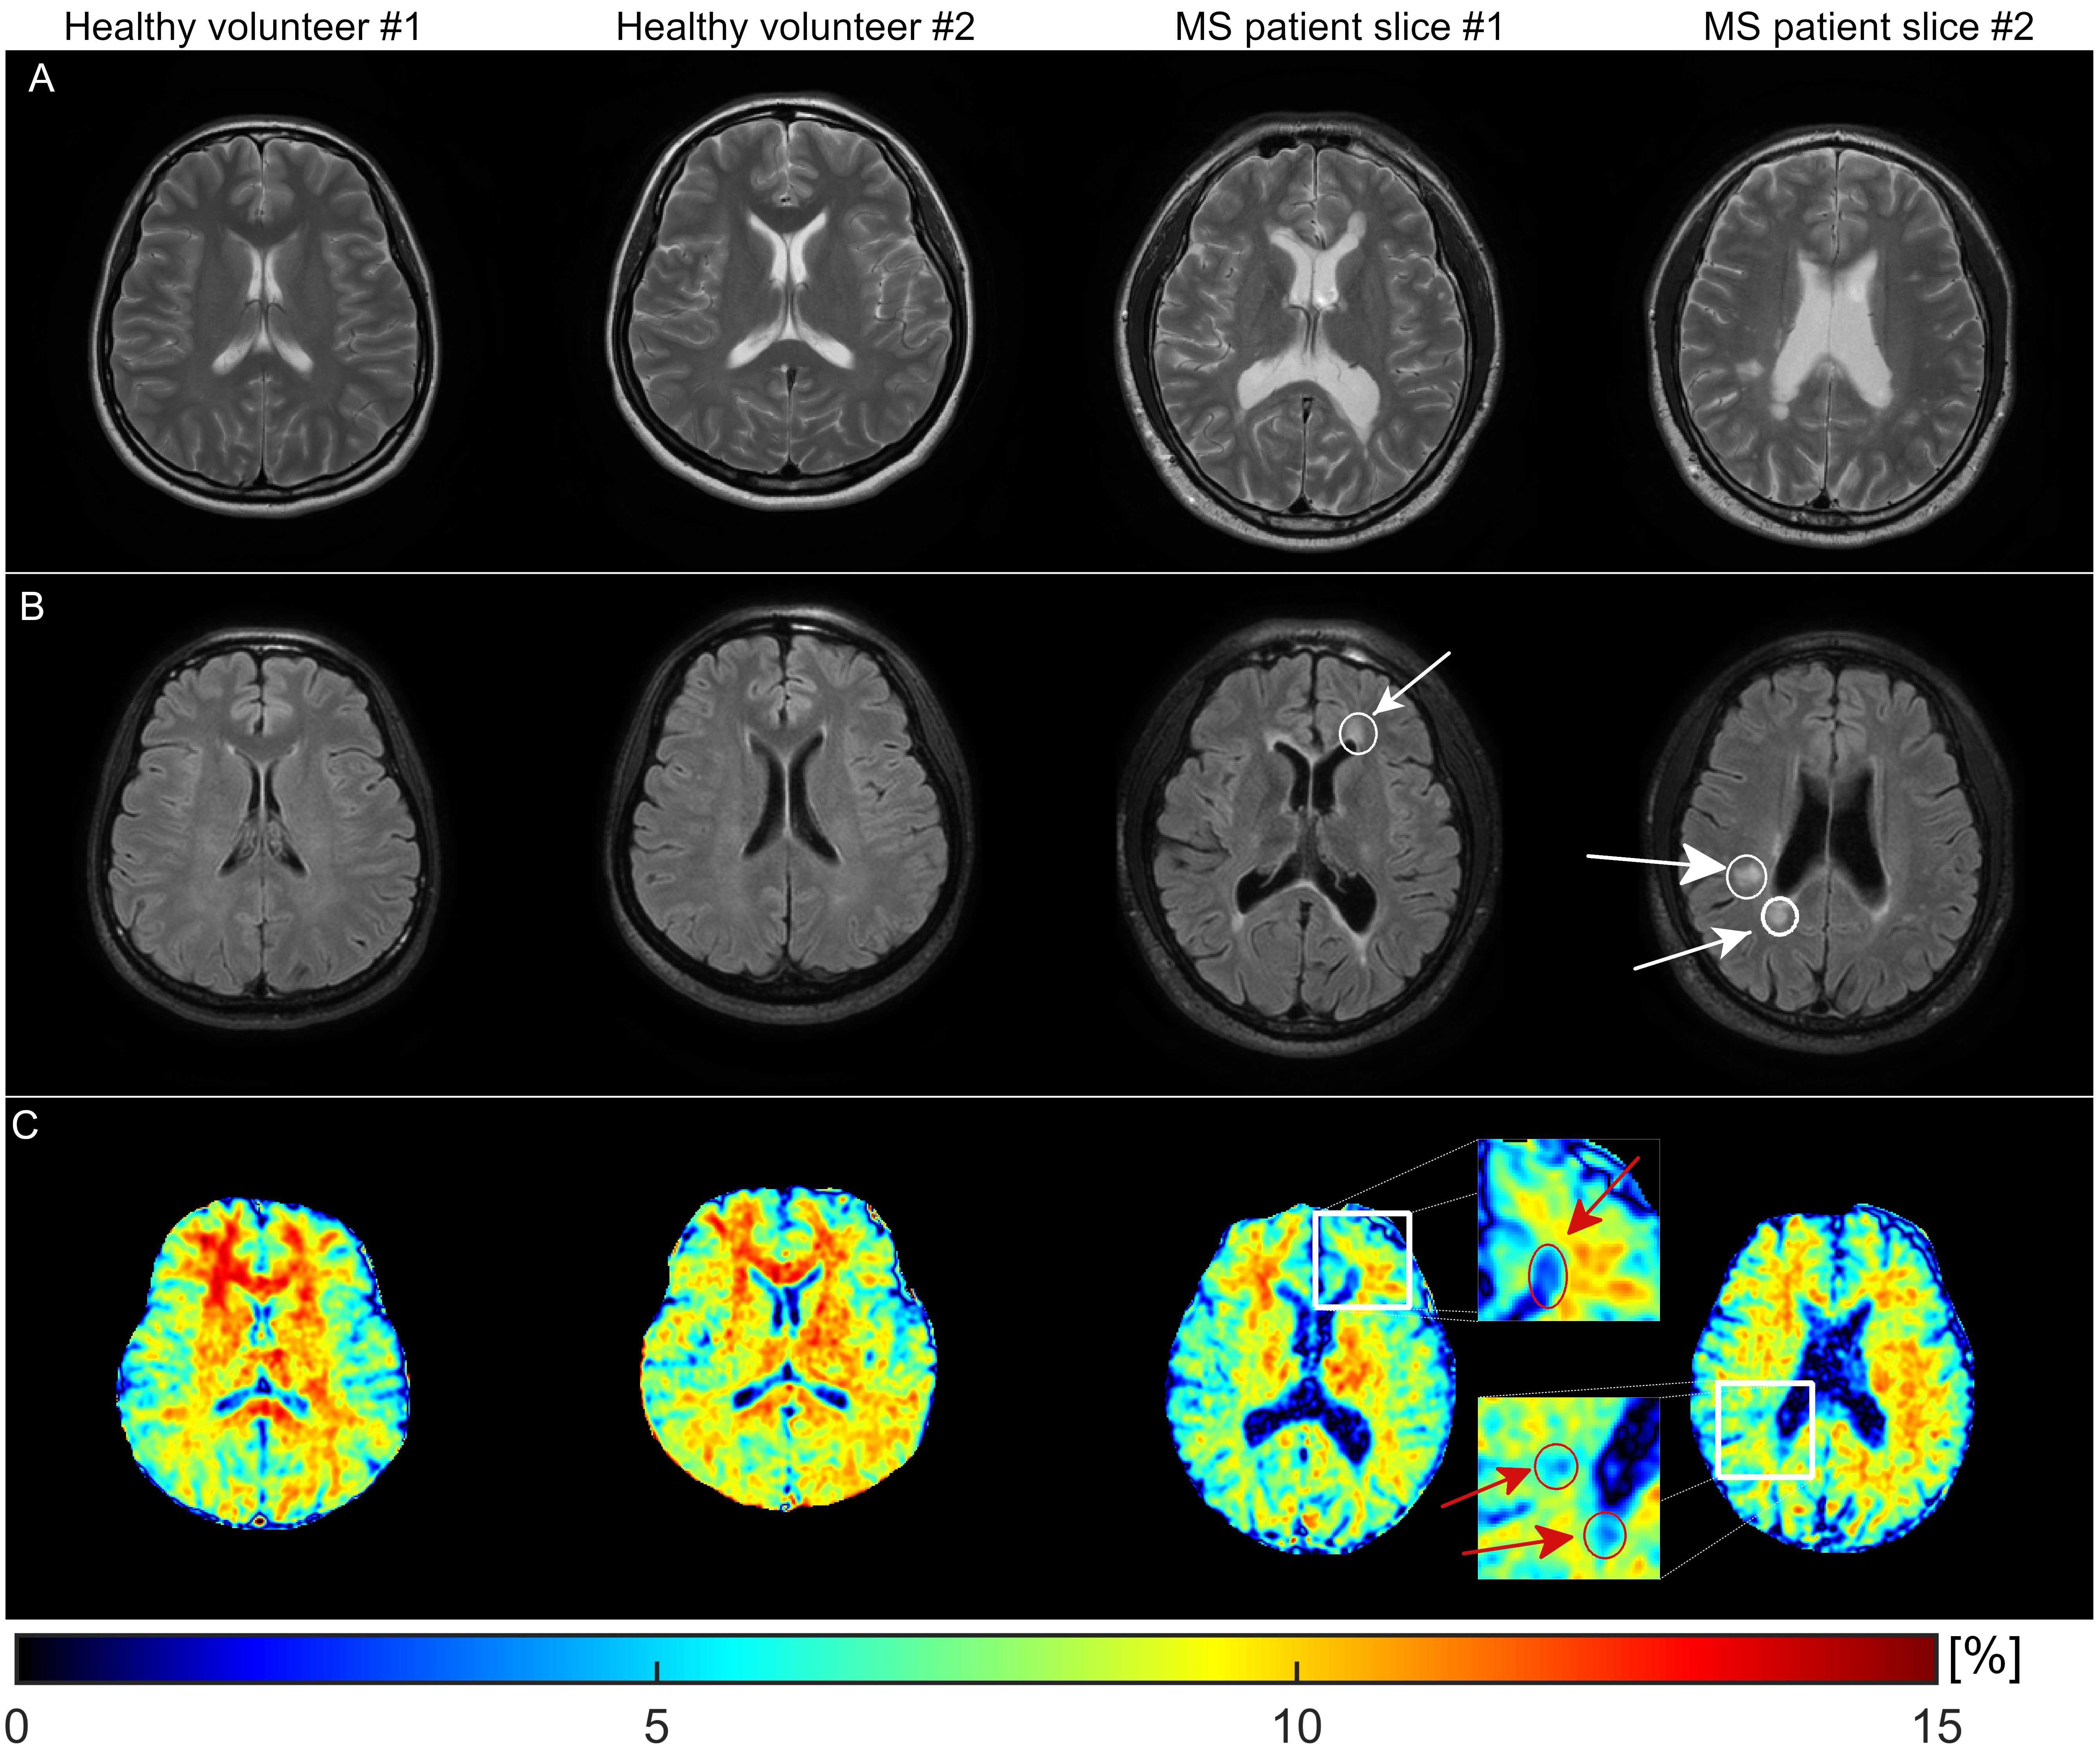

Figure 2 shows the simulation results. It shows that Rmpfsl obtained by our proposed fast MPF-SL approach is approximately a linear function of MPF. Figure 3 shows the results from first phantom study. Note Rmpfsl obtained by the fast MPF-SL method increases with agarose concentration. Figure 4 shows the results from second phantom study. Note Rmpfsl results are comparable when the agarose concentration was same, regardless of MnCl2 concentration. Besides, Rmpfsl results are comparable when using conventional and fast MPF-SL method. Figure 5 shows the in vivo results. Note the MPF decreases at the lesions from the RRMS patient, which suggests the demyelination at these lesions. Compared to two healthy volunteers, the brain MPF value of this RRMS patient shows overall decreases.

Figure 5: Typical slices of A: T2W images; B: FLAIR images and C: MPF maps from 2 healthy volunteers and 1 RRMS patient. Close-up of MPF map around the lesions were also shown in the figure. Note the significant decrease of MPF at the lesions from the RRMS patient. The arrows show the lesions which have reduced MPF value.